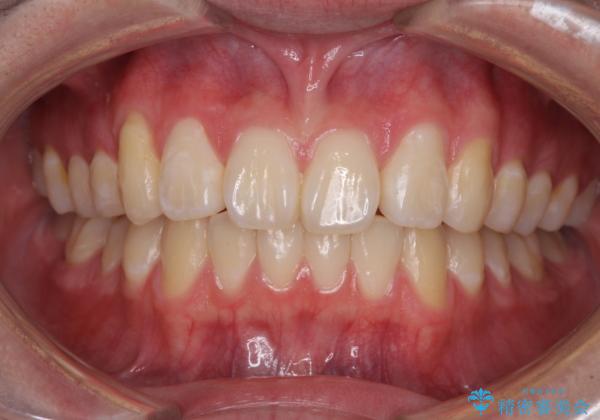

- 八重歯を気にして来院された高校生の患者様です。

ボディーコンタクトの激しい部活動を行っているため、補助装置とインビザラインを用いて、部活動を継続しながら治療を行うこととしました。

八重歯を効率よく改善するため、補助装置を使用して上顎の奥歯を後方に移動させました。

部活動をしながらでしたが、マウスピースをしっかりと装着してくださったので、1年半程度で終了することができました。